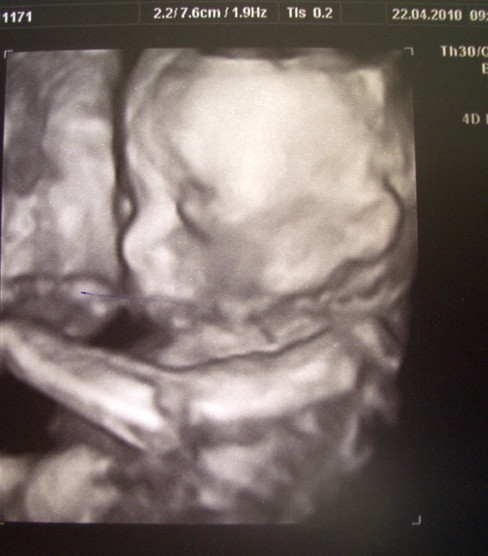

Zdjęcia USG naszych Fasoleczek:))

Oto nasza Kaska :)

Kaska.jpg